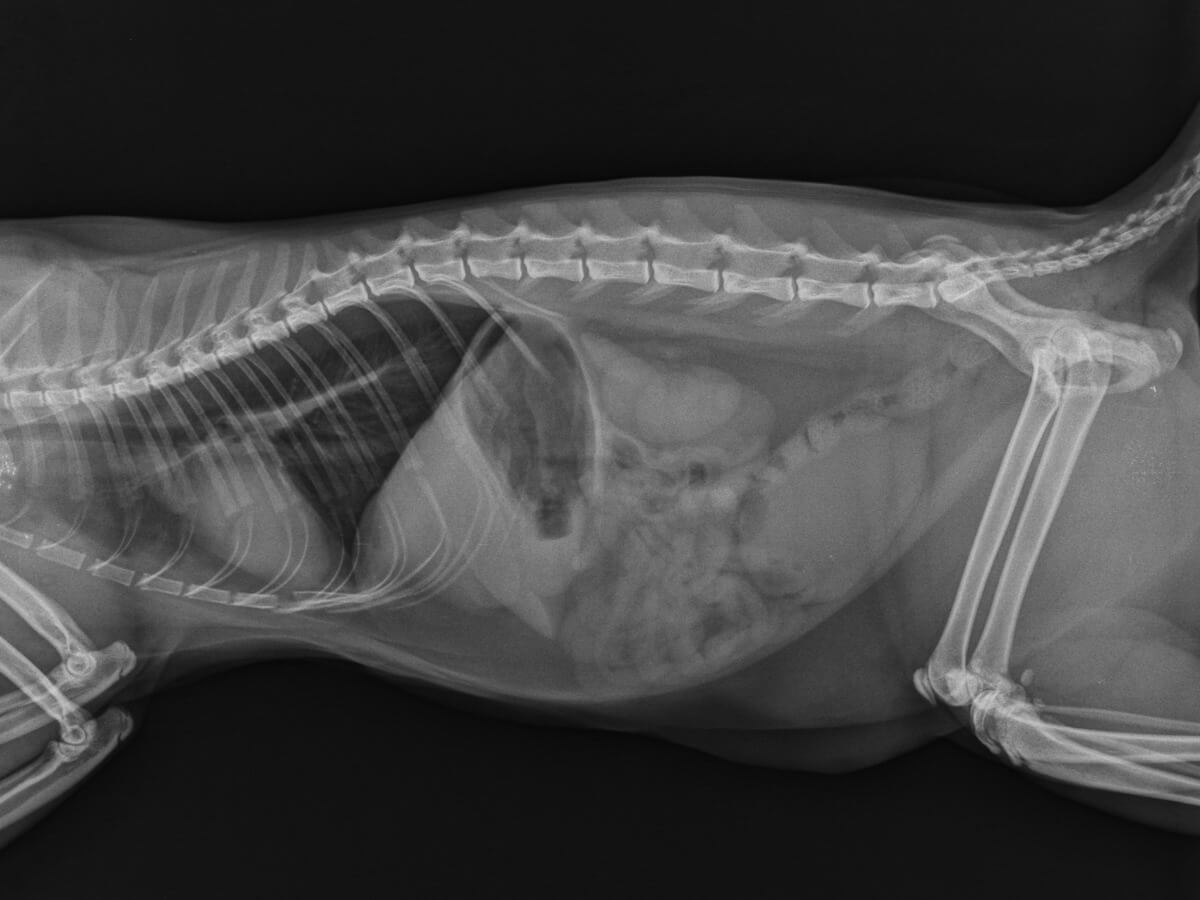

Certains chats ont des calculs dans les reins et ne présentent aucun symptôme. Dans ce cas, il est courant de trouver des calculs dans une partie des voies urinaires de l’animal lorsqu’un test aux rayons X est effectué pour une autre raison. Cependant, certains chats développent des signes cliniques. Parmi eux, figurent les suivants :

Une fois dans la clinique, le professionnel suspectera des urolithes à partir des symptômes ou après une palpation directe. Si un calcul est détecté, divers tests d’imagerie seront nécessaires pour confirmer le diagnostic. Les rayons X détectent les urolithes jusqu’à 3 millimètres de diamètre, mais d’autres techniques d’imagerie, comme les ultrasons, peuvent également être utiles.